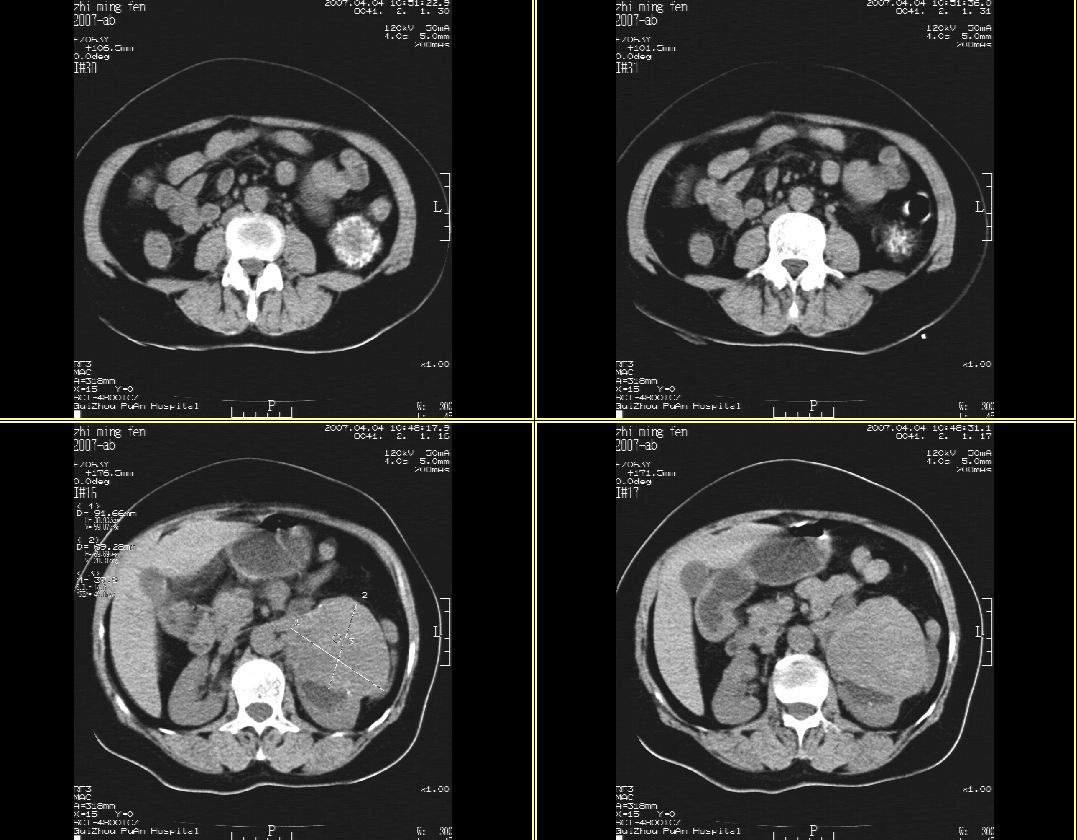

以下是引用hhcckk在2007-4-9 9:18:00的发言:[br]我认为就是一个病灶,病灶上端密度较均匀,下方有明显的钙化,部分呈不完全的环状,考虑肾癌[br]1、肾癌的特征性ct表现为肾实质的占位,局部隆起外突[br]2、肿瘤内的钙化常见,多发生在肿瘤内部,也可以在肿瘤周边呈弧型或不完全的环行钙化[br]3、最常见的三大症状,血尿,腰痛,包块此病人也较符合,增强吧

以下是引用swyyy2007在2007-4-9 18:42:00的发言:[br]支持左肾癌累及肾窦肾盂,左肾积水 [br] [br]